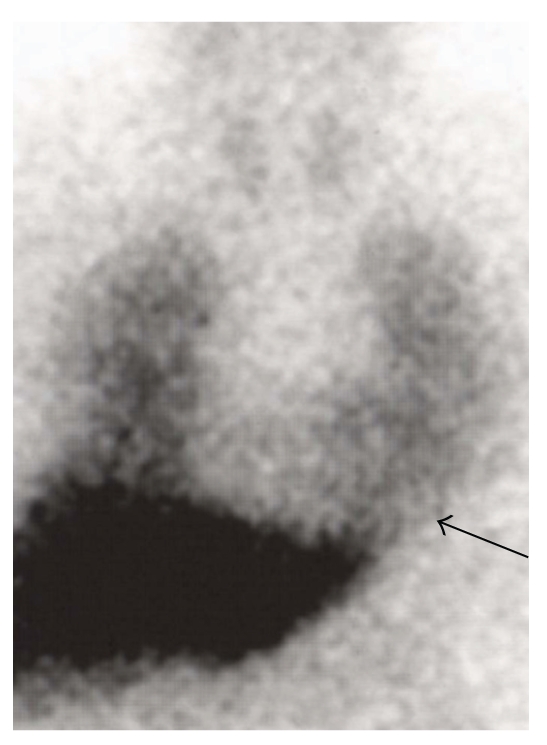

Figure 3.

MIBG scintigraphy in akinetic rigid PD. MIBG scintigraphy in a 65-year old male patient with akinetic rigid type of PD, Hoehn and Yahr stage I. There is hardly any myocardial MIBG uptake (black arrow).

Myocardial MIBG uptake correlates with motor symptoms in PD; patients with tremor dominant PD reveal a significantly higher MIBG uptake (Figure 2) than patients with the hypokinetic rigid type of PD at each Hoehn and Yahr stage (Figure 3; [38, 52]). Myocardial MIBG uptake correlates significantly with the severity of hypokinesia but not with the extent of resting or postural tremor [19, 20, 38].